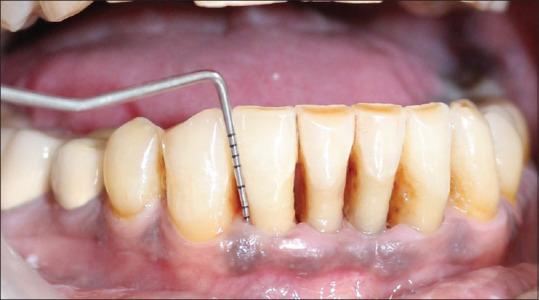

A total of 16 known cases of chronic Periodontitis patients who were suffering from type 2 DM were allocated into two groups. The test group ( = 8) was treated with standard scaling and root planing (SRP) along with PDT while the control group was treated with SRP alone. Various clinical parameters assessed were plaque index, gingival index, pocket probing depth, clinical attachment level, and Glycated hemoglobin level at baseline and 90 days after therapy.

At the end of the study, both the groups showed improvements with regard to all clinical and glycemic parameters compared to baseline. However, the test group presented statistically significant favorable results (all < 0.05).

将1共6例已知患有2型糖尿病的慢性牙周炎患者分为两组。试验组( = 8)接受标准龈上洁治和根面平整(SRP)联合PDT治疗,而对照组仅接受SRP治疗。评估的各种临床参数包括基线时以及治疗后90天的菌斑指数、牙龈指数、牙周袋探诊深度、临床附着水平和糖化血红蛋白水平。

在研究结束时,与基线相比,两组在所有临床和血糖参数方面均有改善。然而,试验组呈现出具有统计学意义的良好结果(所有 < 0.05)。